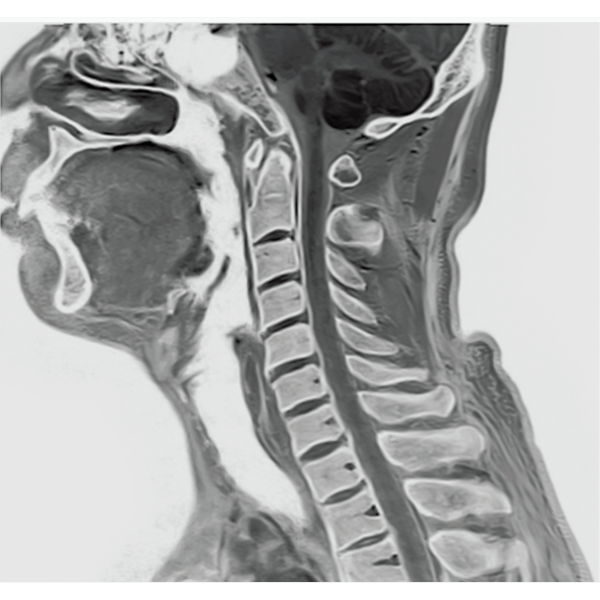

IP-RAPID×DLR PlusはVolumeScanやRadialScan、HalfScanといった基本撮像に加え、MultiContrastScanのFatSepやDWIなど多くの撮像法でお使いいただけます。広範囲DWIやWhole Spine撮像など時間のかかるWide Scanにも併用でき、多くの部位で従来よりも詳細な情報を得ることができます。

2DFSE

3DGrE Bone Imaging

3DPBSG

2DGrE

2DBASG